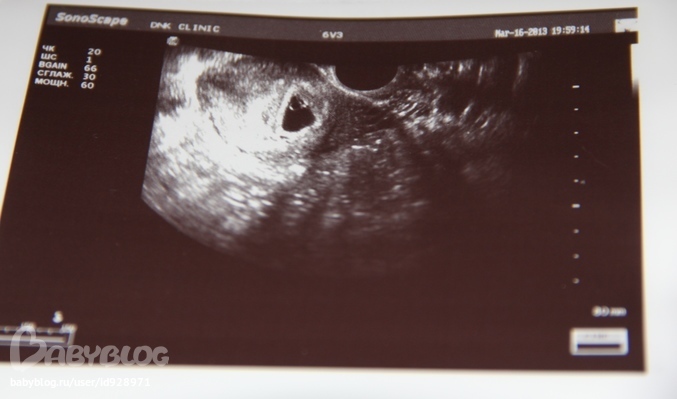

Прилагаю фоточки моей бусинки и заключения. Как вы думаете, по заключению все хорошо? Все размеры нормальные? КТР почему-то 0,3мм, а на словах она мне сказала 3 мм. Может, ошиблась, когда печатала?